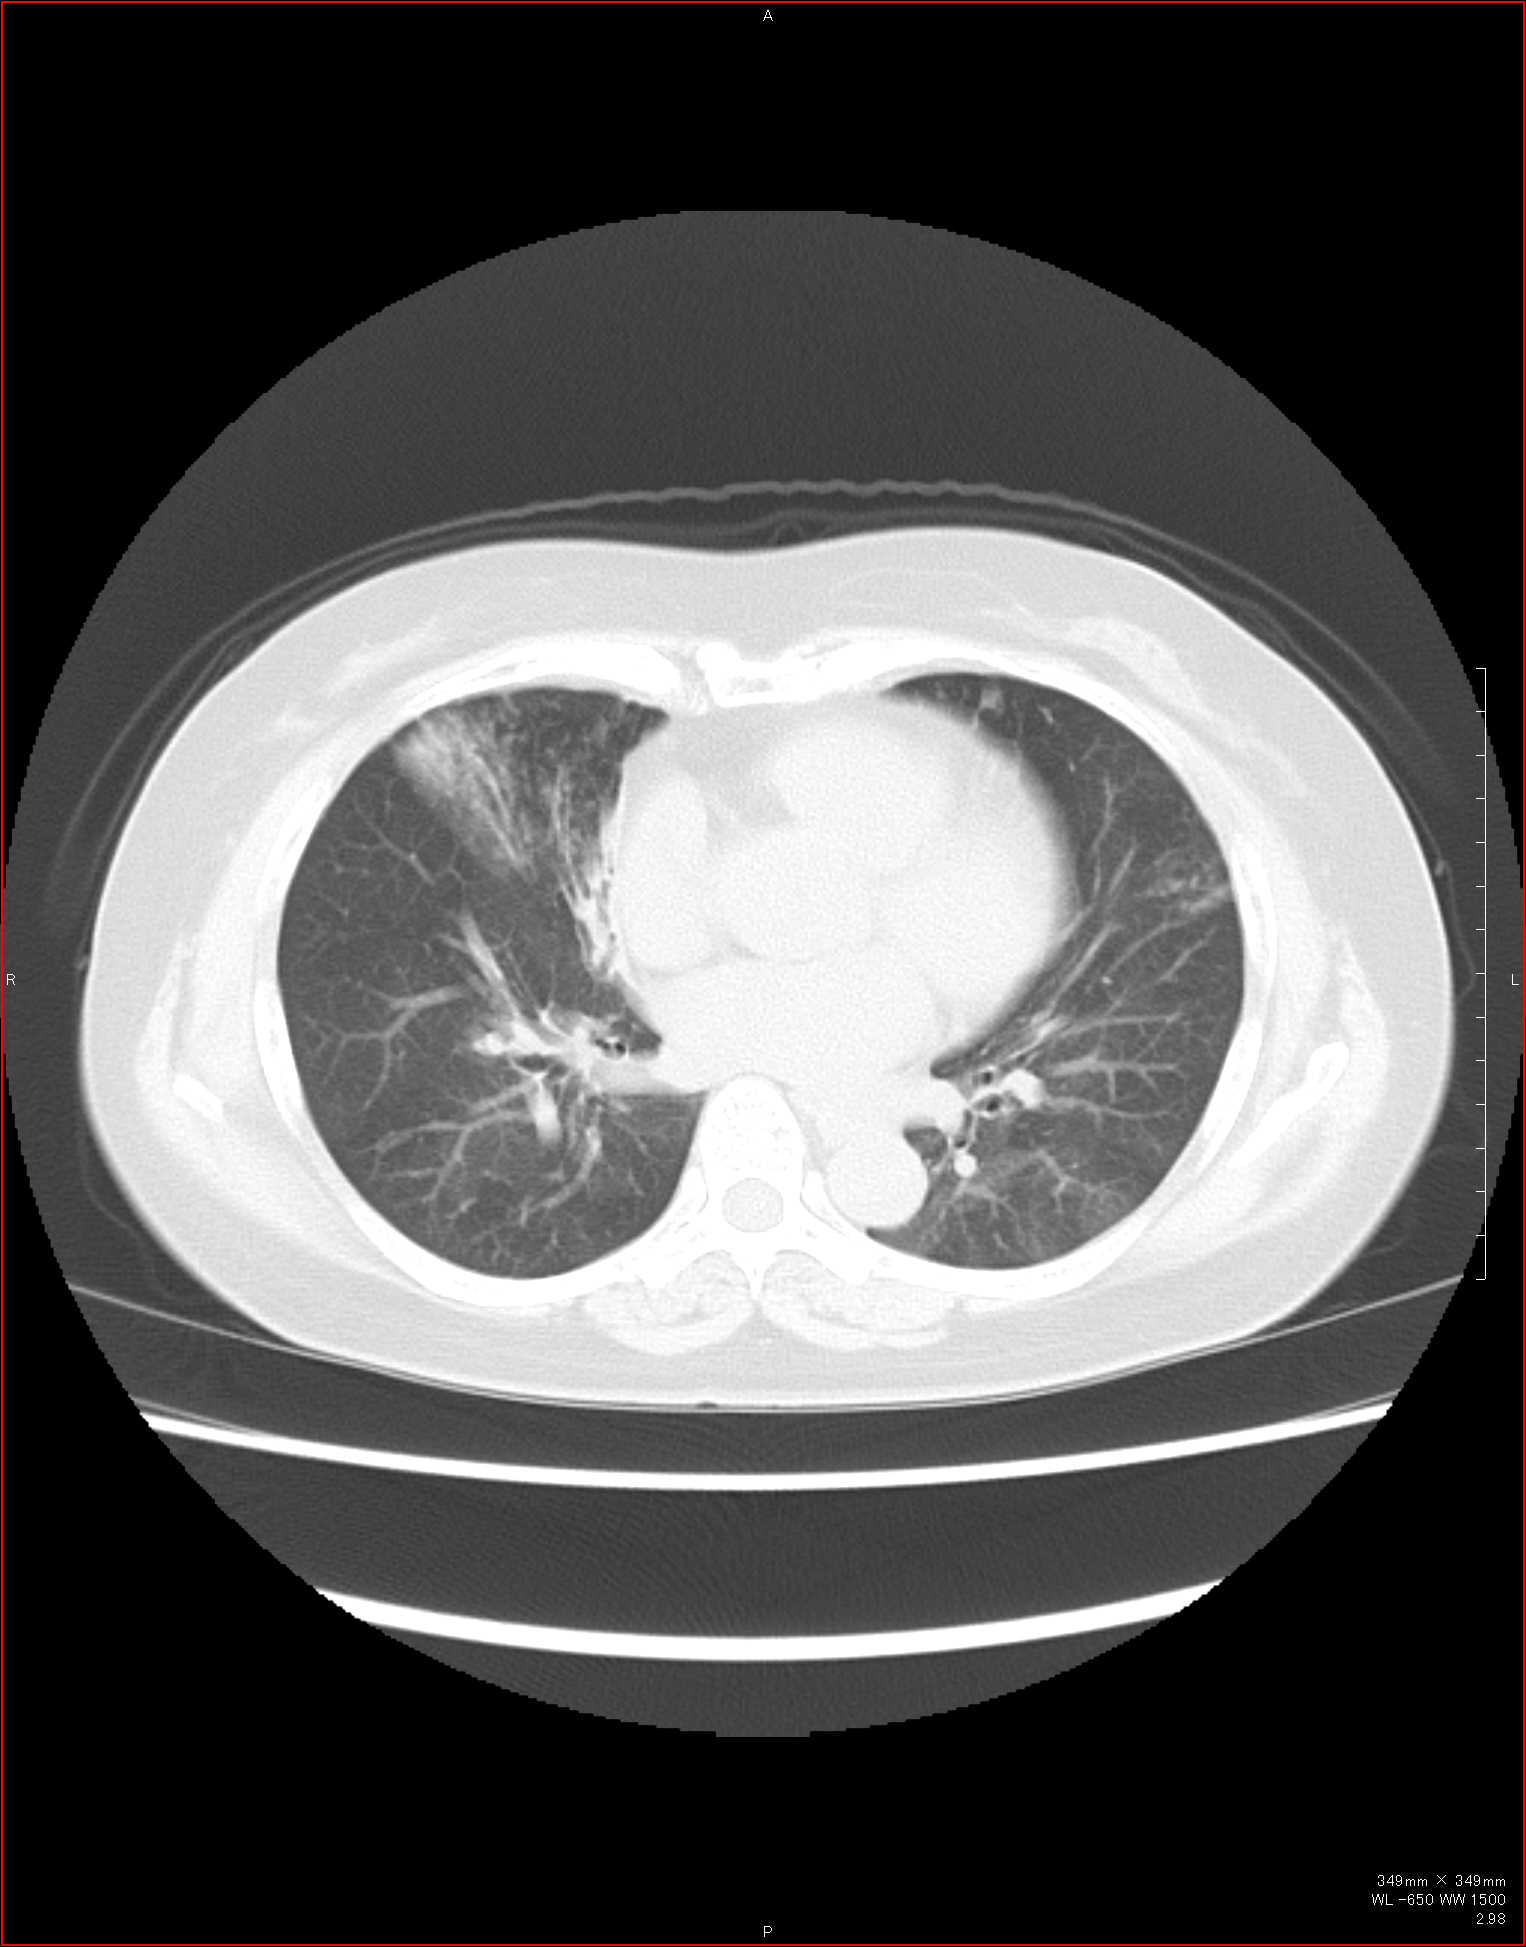

CTで見ると…

気管狭窄ですね。こういう所見もレントゲンで捉えることができるのです。